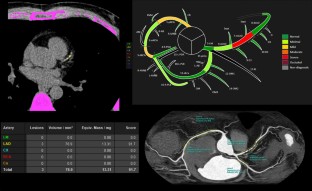

Fig. 3